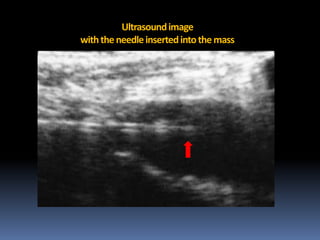

US Guided FNA

Ultrasound image

with the needle inserted into the mass

The specimen was diagnosed as Schwannoma

Ultrasound image with theneedle inserted into the mass

• 58.

The specimen wasdiagnosed as Schwannoma